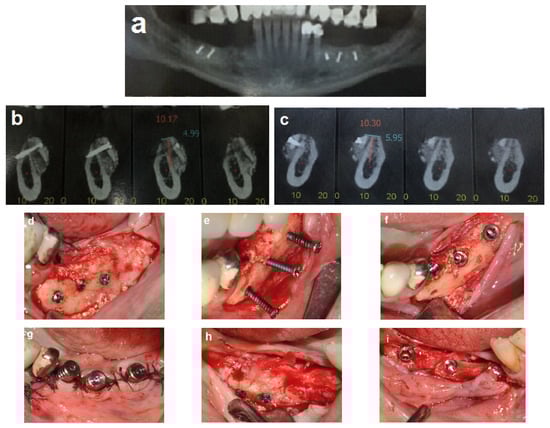

Follow-up was scheduled three times every two weeks, then monthly. Partial exposure of the graft occurred at four weeks on the right side but was successfully managed without compromising the augmentation outcome. A CBCT scan was obtained after four months to assess the bone gain (Figure 4a–c). Dental implants were placed 4 months after the procedure (Figure 4d–i). A fixed prosthesis was delivered four months after the implant placement. This case was followed for 10 years (Figure 5).

Figure 4.

Reentry at 4 months. (a–c) CBCT post-op demonstrating significant horizontal bone gain. (d) Left-side view, showing excellent integration of the bone blocks and the width of the new bone demonstrated by the length of the removed fixation screws (e). (f,g) Placement of three implants on the left side. (h) New bone volume on the right side. (i) Placement of three implants on the right side.

Figure 5.

Follow-up. (a,b) Ten-year follow-up post-loading, showing the implant at the recipient site with no marginal bone loss.